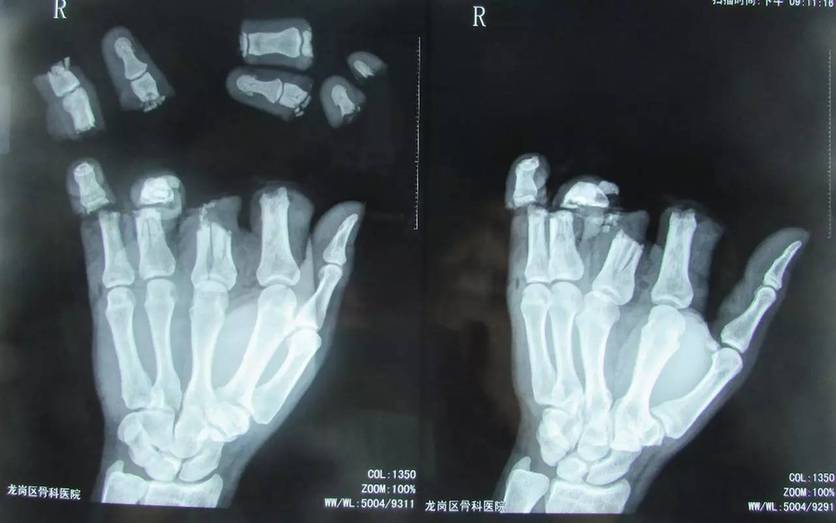

惨不忍睹!4根手指碎成8节!

事发4月12日下午,深圳光明新区一家工厂内,一名四十多岁的男性工人不慎被机器压伤右手,除大拇指外,4根手指碎成8段。